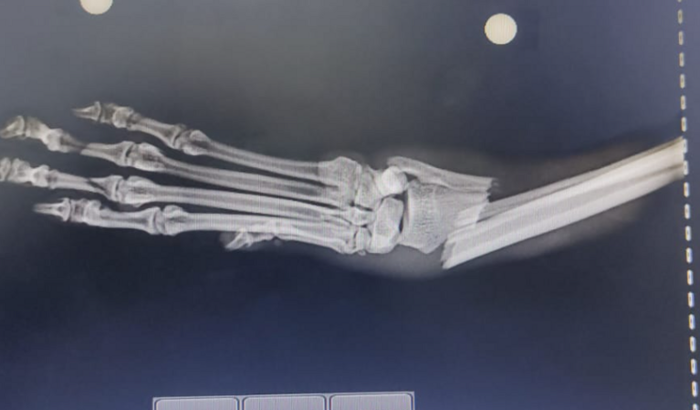

Eu sou o Caramelo e minha dona criou essa vaquinha, pois cai da área de serviço da minha casa e quebrei o rádio e a ulna da minha pata direita como podem ver na imagem, será necessário fazer uma cirurgia para colocar uma placa de titânio e eu poder voltar a brincar e fazer minha arte (com moderação).